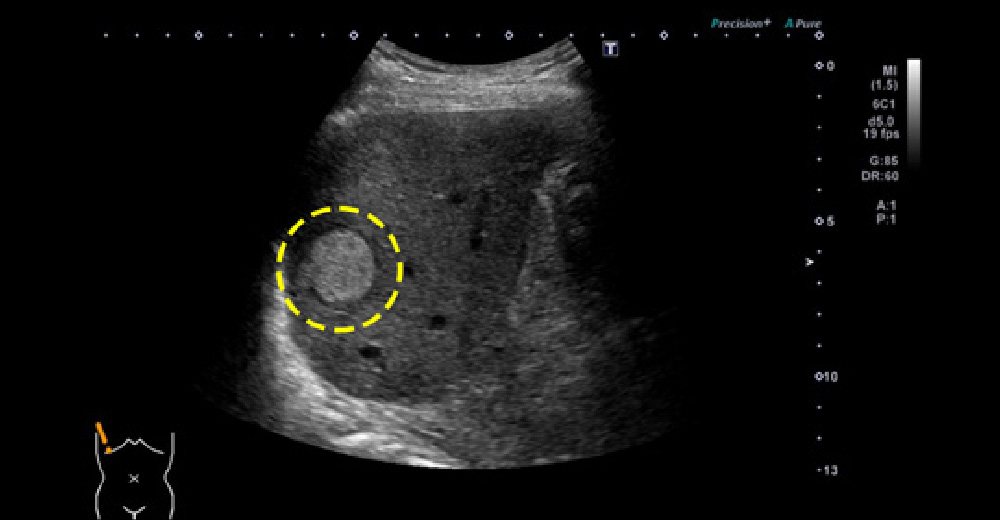

糖尿病併存脂肪肝に、発生した肝がん 糖尿病併存脂肪肝に、発生した肝がん

糖尿病併存脂肪肝に、発生した肝がん